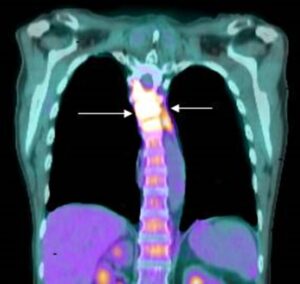

Bone is the third most frequent site for cancer to spread. Nearly all types of cancer can spread (metastasize) to the bones.  But some types of cancer are particularly likely to spread to bone, including breast cancer, kidney cancer, lung cancer, melanoma, ovarian cancer, and prostate cancer.

Bone metastasis can occur in any bone but more commonly occurs in the spine, pelvis and thigh. Bone metastasis may be the first sign that you have cancer, or bone metastasis may occur years after cancer treatment.